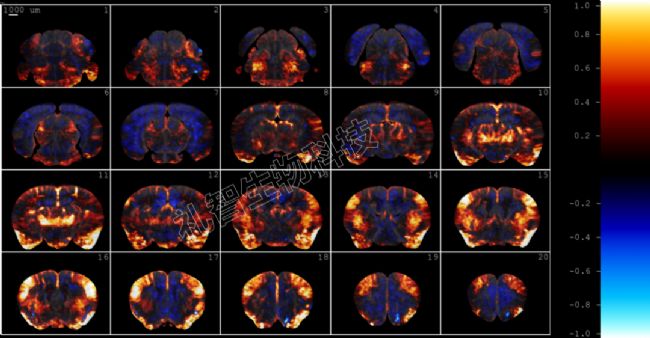

圖2. 飲水行為的全腦激活地圖。圖來源:禮智生物科技

對 8 個 trial 給水時間段作平均的相對CBV圖,得到相似的結(jié)果。

圖3. 平均給水時間段內(nèi)的相對CBV圖。圖來源:禮智生物科技

可以看到給水時間段內(nèi),嘴部和鼻子相關(guān)的感覺皮層明顯的激活,除此以外,初級、次級運動皮層、紋狀體、丘腦、中腦內(nèi)側(cè)膝狀體, p1Rt網(wǎng)狀結(jié)構(gòu)等均出觀察到明顯激活,再往后腦橋網(wǎng)狀核也出現(xiàn)從前至后的大范圍激活。另外也有很多腦區(qū)出現(xiàn)明顯的負相關(guān),包括前扣帶回皮層、背側(cè)紋狀體、背側(cè)海馬、下丘腦等等。